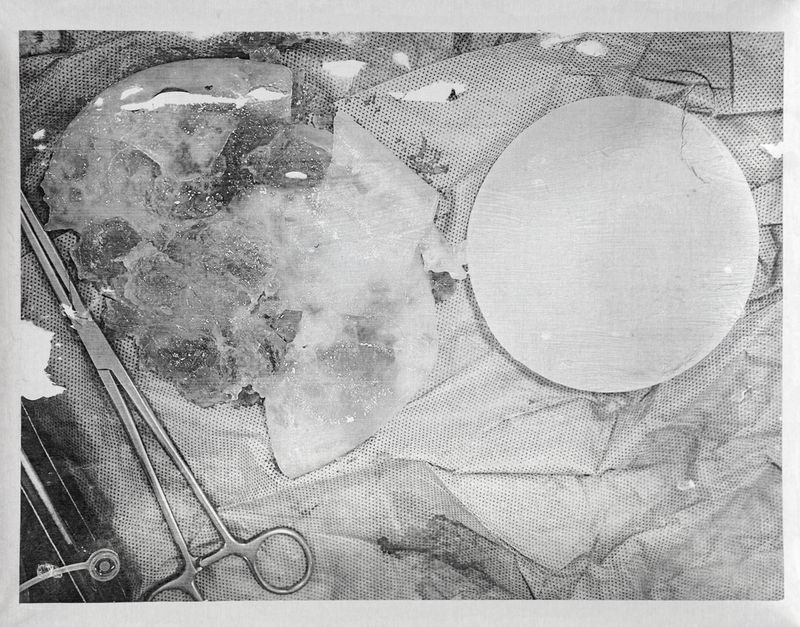

Implants removed from María Machado during explantation surgery, with surgeon Andrés Ocando in July 2025.Photo transfer on embossed aluminum plate